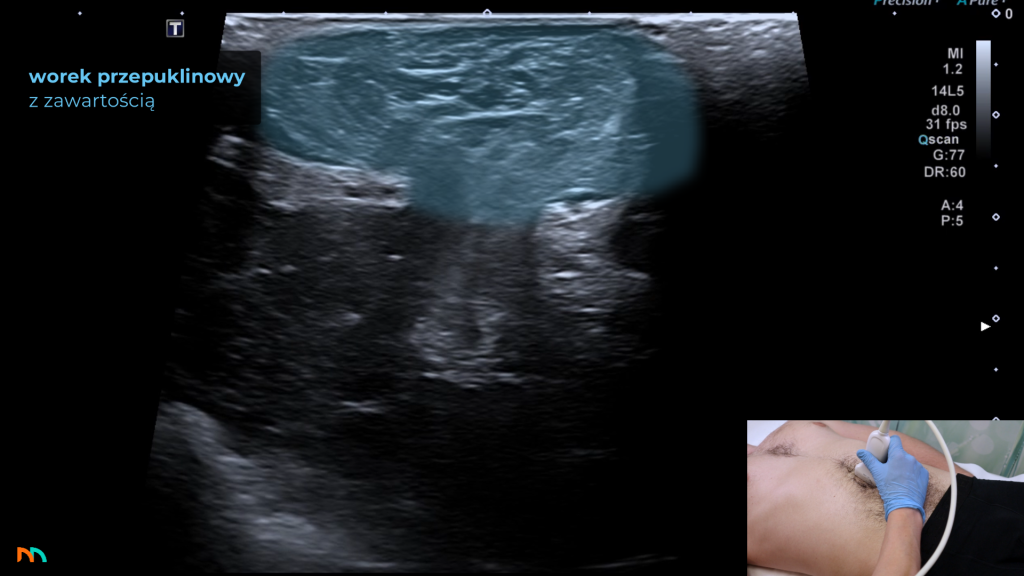

Z ultrasonograficznego punktu widzenia taka przepuklina składa się z:

- wrót przepukliny

- worka przepuklinowego

- oraz jego zawartości